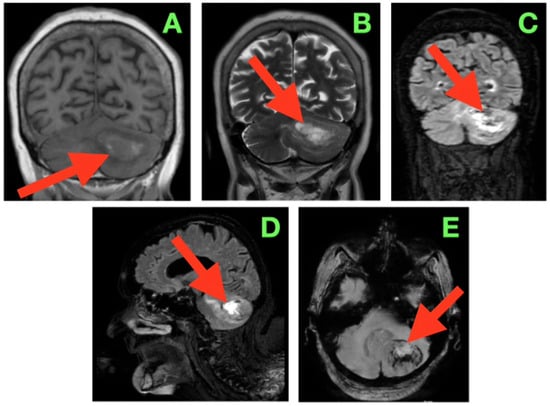

A non-contrast cranial computed tomography (CT) scan performed within two hours of dural closure (Figure 2) demonstrated not only complete evacuation of the space-occupying tumor but also that the left cerebellar hemisphere was decompressed. At the inferior cerebellar convexity (A) of the axial sections, the resection cavity occupied the expected shape of the left neocerebellar hemisphere posteriorly, and the margin of the craniectomy constituted the right lateral wall. There was no residual mass effect on the foramen magnum. More rostrally (B) in the axial images, the cavity shape remained foramellous and adhered to the superior cerebellar surface under the tentorium with the bridging veins intact, and without hyperdense foci, suggesting venous thrombosis. At the level of the fourth ventricle (C), the shape of the midline vermis was intact, and the ventricle outlet pathways (foramina of Luschka and Magendie) were patent so that CSF could cross these barriers unrestricted to cisterna magna. No intraventricular or parenchymal hemorrhage was detected, and pericavitary hypodensity consistent with mild post-operative edema was <4 mm thick. The brainstem contours, particularly the dorsal pons and middle cerebellar peduncle, were crisp, undistorted, and undelimited. Although a post-operative gadolinium-enhanced MRI (early within 48–72 h after surgery) is often helpful in demonstrating the post-operative resection cavity and providing definition of surgical margins for stereotactic radiosurgery planning, no such image was obtained in this case. This patient stabilized neurologically and continued to improve in an uneventful manner with no evidence from either imaging studies or clinical findings to necessitate an urgent reassessment using intravenous contrast. Due to the patient’s advanced age and pre-existing cognitive impairments, the care team felt that avoiding the initial post-operative transportation and potentially sedating the patient would help to prevent additional physiologic stresses to the patient.

Figure 2. Immediate post-operative non-contrast CT scan. (A) Axial section through the inferior cerebellar convexity showing the post-operative resection cavity occupying the left neocerebellar hemisphere (arrow), with smooth posterolateral margins abutting the suboccipital craniectomy window. The inferior wall terminates above the foramen magnum, and no residual mass effect on the cervicomedullary junction is present. (B) Axial section at the level of the superior cerebellar hemisphere and tentorial undersurface demonstrating the superior margin of the cavity (arrow) in close apposition to the tentorial surface, with preserved bridging veins and absence of hyperdense foci indicative of venous thrombosis or parenchymal hemorrhage. (C) Axial section through the fourth ventricle depicting a midline vermis contour preserved in its entirety, with the cavity’s medial border (arrow) respecting the paravermian zone. The outlets of the fourth ventricle (foramina of Luschka and Magendie) are patent, and CSF freely communicates with the cisterna magna. No evidence of intraventricular hemorrhage, hydrocephalus, or brainstem distortion is observed.